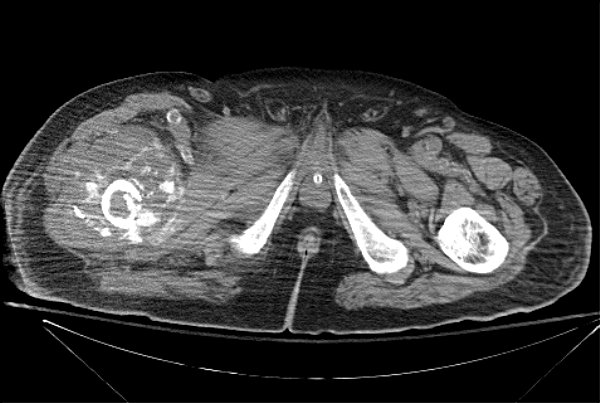

Return to Pathologic Fracture (Femur)